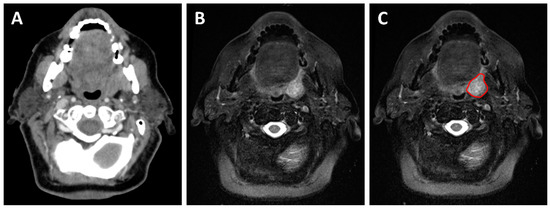

2.1. Local Extension